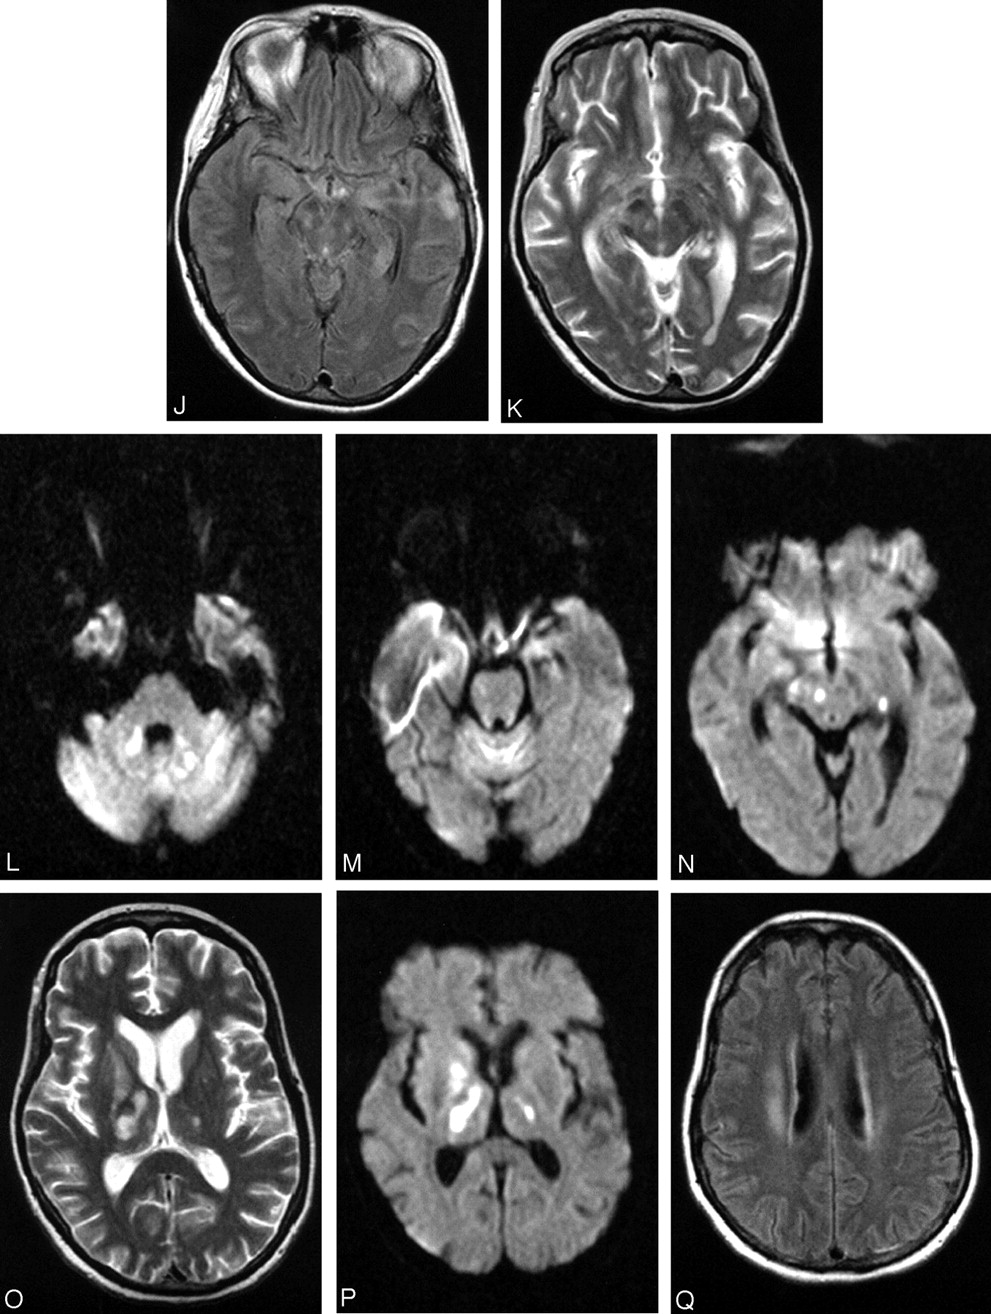

Patient 17, a 49-year-old woman with history of non-Hodgkin lymphoma in remission presented with fever. Work-up was negative for recurrence. The first MR imaging of the brain shows abnormality in the left mesial temporal lobe on trace DW image (A) and ADC (B), though the finding is subtle on the FLAIR sequences (C). At the time of imaging, the findings raised the question of herpes encephalitis, for which the patient was originally treated. Following deterioration of the mental status and development of upper extremity weakness, a second MR imaging was obtained. The abnormality is now apparent on the FLAIR sequences and has progressed to involve not only the contralateral mesial temporal structures, but also the substantia nigra (D), as well as the mesial and dorsal aspect of the thalami (E). Further clinical deterioration with established “polio-like” symptoms prompted a new MR imaging 11 days later, which demonstrated new areas of involvement with resolution of improvement of prior lesions. Images of this MR imaging show increased signal intensity in the dentate nuclei on FLAIR (F) and DW (G) images and right thalamus on FLAIR image (2 hours) and DW image (I) and improvement of the mesial temporal lobe and midbrain abnormalities (J). Focus of T2 hyperintensity is seen in the right red nucleus on FSE T2-weighted image (K). On J, note site of biopsy in the lateral aspect of the left temporal lobe that was negative for herpes encephalitis. The fourth MR imaging was obtained upon patient’s discharge to a nursing facility. DW images show increased signal intensity in the cerebellar hemispheres and right branchium pontis (L), vermis (M), and the right red nucleus (N). Cerebellar hemisphere abnormalities were more conspicuous on DW than FLAIR or FSE T2-weighted images. FSE T2-weighted (O) and DW (P) images through the level of the basal ganglia demonstrate persistent abnormality in the right thalamus and new lesions in the right globus pallidus and left thalamus, whereas the FLAIR image demonstrates involvement of the right corona radiata (Q) as well.

Patient 11, a 51-year-old man post renal and pancreatic transplant with recent mosquito exposure. Axial DW images show patchy areas of increased signal intensity in the periventricular white matter and left cerebral peduncle (A) as well as corona radiata and corpus callosum (B). Axial FLAIR sequences demonstrate subtle abnormalities in the left mesial temporal lobe, both cerebral peduncles, more pronounced in the left one (C), and both thalami and left globus pallidus (D). Diffusely increased signal intensity is also present in the deep hemispheric white matter (D and E). Histopathology (F) shows the hippocampus with marked perivascular (bold arrow) lymphocytic inflammation (hematoxylin and eosin; original magnification 200×). Histopathology (G) demonstrates white matter infarct with necrosis, macrophage and early cavitary changes (cavitation delineated by arrows) (hematoxylin and eosin; original magnification 200×).

Midbrain involvement was noted in only 3 patients (Table 1); signal intensity abnormalities present in the cerebral peduncle and substantia nigra (Fig 2D, -J, and -K), as well as red nucleus (Fig 2N), are in accordance with prior case reports on Japanese and St. Louis encephalitides (13, 15). Involvements of the pontine tegmentum (Fig 1A and -B) and superior cerebellar peduncles (Fig 1C) were the first abnormalities to be noticed in one of the patients (2), who became ventilator dependent and progressed to develop flaccid paralysis. There were 4 patients who presented at some point with extremity weakness. All, with one exception (17), had MR imaging studies of the spine; abnormalities were seen in the gray matter and particularly the ventral horns in 2 of them, whereas enhancement of the conus medullaris and the cauda equina was seen in all 3. Prior reports have associated the flaccid paralysis with enhancement around the conus and along the cauda equina (2, 3). Anterior myelitis apparently contributes to the clinical picture as well (Figs 1E–G and 4A and -B). Abnormalities in the dentate nuclei, cerebellar white matter, and cortex were present in only one patient (Fig 2F, -G, -L, and -M) and are depicted on one of the follow-up MR imaging studies coinciding with newly developed “polio-like” symptoms. Unfortunately the patient’s spine was never imaged, so whether there were any additional findings of anterior myelitis and/or radiculitis remains unknown.

Imaging findings are corroborated by pathologic findings. Reports in the pathology literature describe the presence of microglial modules but no evidence of necrosis in the hippocampus (16, 17). Sampson et al (17) described the presence of microglial nodules in the gray and white matter, distributed in the basal ganglia, thalami, and medulla, as well as the frontal cortex and molecular layer of the cerebellum. In one case, they did comment on more pronounced involvement of the medulla. Perivascular mononuclear inflammation was found more often in the gray matter vessels. They also commented on the most frequent involvement of the brain stem in WNV in comparison with St. Louis encephalitis. We noticed variable involvement of the cortex specifically in the temporal lobe (5 patients) and cerebellum (one patient). Remarkably, MR imaging of the brain of the very first patient (1) to be diagnosed with WNV encephalitis at our institution showed a single patchy area of increased signal intensity seen on FLAIR and DW images, with minimally low signal intensity on the apparent diffusion coefficient (ADC) that had been interpreted as subacute infarct. In retrospect, this finding might indeed represent inflammatory changes as well (Fig 5A and -B).

The fact that the perivascular inflammation is more often encountered in the gray rather than white matter may reflect on the fact that only 2 of our patients (Table 1) had white matter involvement, both with higher likelihood of impaired immune system and one of them only on late follow-up studies. It is worth commenting on one of these patients (11) who presented with numerous, scattered areas of restricted diffusion throughout the deep hemispheric white matter (Fig 3A and -B). It was this deep and extensive distribution of signal intensity abnormalities that prospectively raised the question of an inflammatory/infectious process. It has been reported that abnormalities on the DW images of variable degree are present in encephalitis (18). Nevertheless, autopsy of the patient revealed frank ischemic changes (subacute infarcts) in the deep hemispheric white matter (Fig 3G). Although pathologists have commented on perivascular infiltration, they had not found any evidence of vasculitis in the 4 cases of WNV on which they reported (17). Abnormalities in the corona radiata in the second patient (17; Fig 2Q) seen on the last follow-up MR imaging could in fact be either inflammatory or ischemic in nature. Both patients had in common significant past medical histories, renal/pancreatic transplant, and non-Hodgkin’s lymphoma, respectively, and both had poor outcomes, with death and severe neurologic impairment, respectively. Regardless of the etiology, ischemic or inflammatory of the diffusion abnormalities in the white matter, whether the white matter involvement represents progression to end-stage disease remains a question. Also under consideration is whether relatively impaired immune status could lead or precipitate such an involvement of the white matter. White matter abnormalities have been reported in Japanese encephalitis also. MR imaging findings in patients with Nipah encephalitis describe almost exclusively white matter abnormalities, at least in early imaging with some involvement of the deep gray matter and cortex on follow-up studies (19, 20). In the patients with WNV we studied, it was the deep gray matter and brain stem involvement that were most often encountered (Table 1).